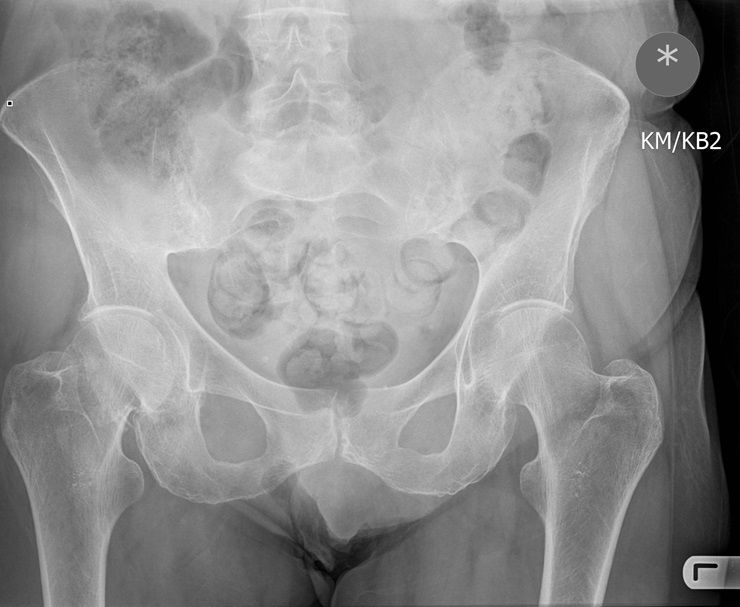

Question 1

Question

Which operation would you chose?

Answer

• THR

• Hemiarthroplasty